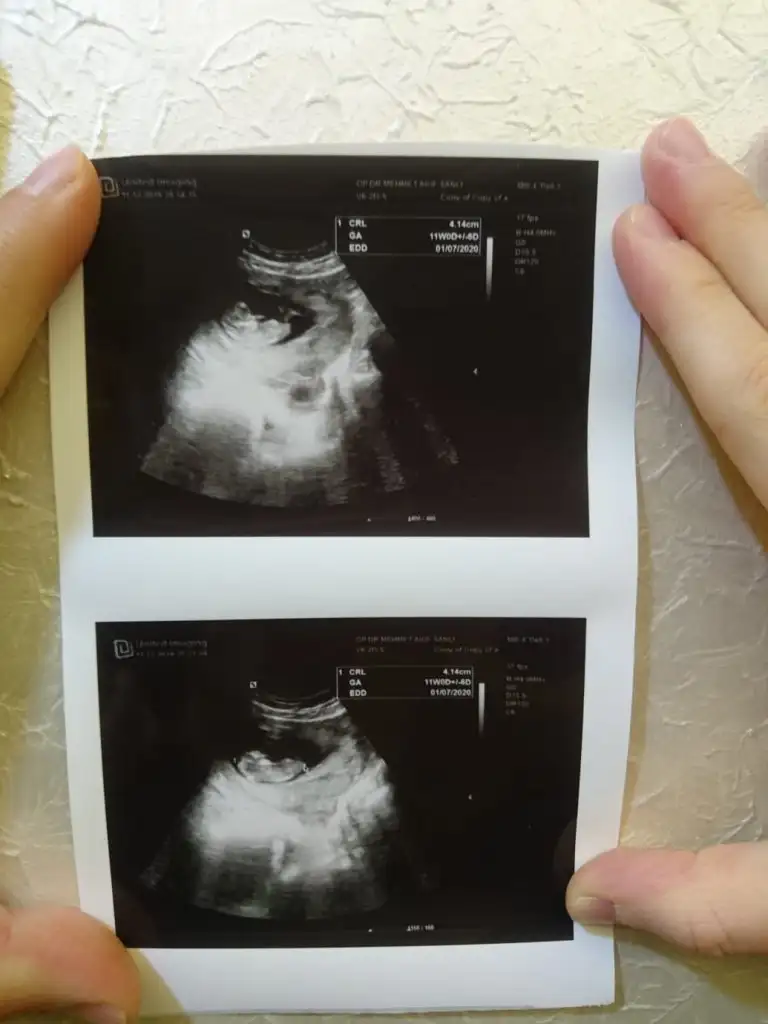

Şimdilik kız gibi gibi diyorum 11 yada 12 hafta paylaşınBu attığım ultrason fotosunda 7 haftalıktı galiba elimde bu yeni attığım da da 10 haftalık henüz gitmedim doktora![]()

Evet ya bide özel hastane olcaktı hiç güzel değildi makinesi doktorda dedi kıza benziyor ama net değil 16 ıncı haftada dicekmiş bakalımNet degil usg ama sanki sanki kız gibi gibi diye ekliyorum![]()